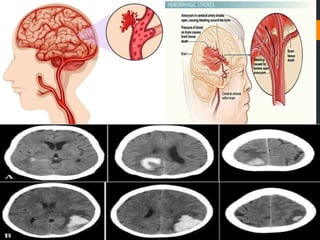

Basic 2 mechanism causing brain damage in

stroke are ischemia and haemorrhage.

Ischemic stroke is when the blood supply is

decreased or ceased.

Haemorrhagic stroke is when there is

vascular compromise.

ISCHEMIC STROKE

• Result of thrombus embolus

occlusion, cerebral infarction,

etc.

• Blood clot or plaque formation.

• Majority of emboli are showered

from the heart affected by

rheumatic heart disease.

HAEMORRHAGIC STROKE

• Rupture or trauma of intra-cerebral

vessels leading to abnormal

bleeding.

• Bleeding into extra-vascular areas of

the brain result into increased

preesure, i.e. ICP.

• Can be of three types intracerebral,

primary cerebral and subarachnoid

haemorrhage.